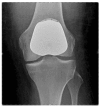

Background: Severe arthritis of the knee is a disabling condition, with over 50,000 knee replacements performed each year in the UK. Isolated patellofemoral joint arthritis occurs in over 10% of these patients with the treatment options being patellofemoral arthroplasty or total knee arthroplasty. Whilst many surgeons believe total knee arthroplasty is the 'gold standard' treatment for severe knee arthritis, patellofemoral arthroplasty has certain potential advantages. Primarily, because this operation allows the patient to keep the majority of their own knee joint; preserving bone-stock and the patients' own ligaments. Patellofemoral arthroplasty has also been recognised as a less 'invasive' operation than primary total knee arthroplasty, facilitating a more rapid recovery. There are currently no published results of randomised clinical trials comparing the two arthroplasty techniques. The primary objective of the current study is to assess whether there is a difference in functional knee scores and quality of life outcome assessments at one year post-operation between patellofemoral arthroplasty and total knee arthroplasty. The secondary objective is to assess the complication rates for both procedures.